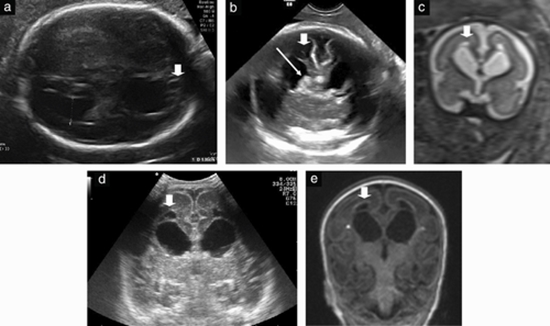

Fetal intraventricular hemorrhage {faces}

We enjoyed reading the recently published article by Dr van der Knoop and colleagues in this Journal, on the additional value of advanced neurosonography and magnetic resonance imaging (MRI) in 56 fetuses at risk for brain damage1. Detection of acquired fetal brain anomalies is a major issue in high-risk fetuses, and multiplanar neurosonography and MRI are helpful modalities in the evaluation of periventricular echogenicity and intraventricular hemorrhage (IVH)1. There are three conflicting and discrepant issues in this article